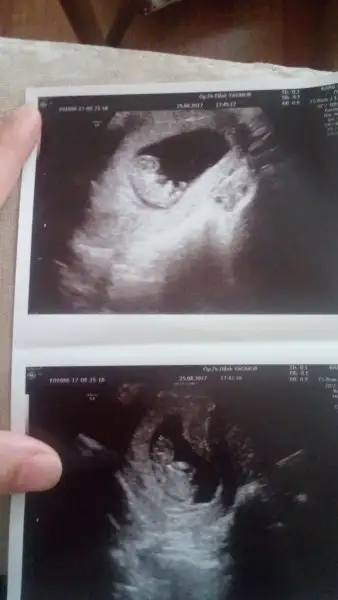

Hadi ya nasil oyle dusundun doktor baya bakti aletleri de guzel ve netti durus yerinden ve kemik halinden kiza benziyor dedi neyse bir ay sabredicem artik :) sagolasin cnm yorum icinALLAH hayırlısı ile gönlündekini versin inşallah ama ben burada erkek bebek görüyorum canım..

Ya masaallah ne guzel sizin ultrason goruntuleriniz nekadar net belirgin ben gidiyorum karincali hicbisey belli olmuyor sozde bide ozele gidiyorum.